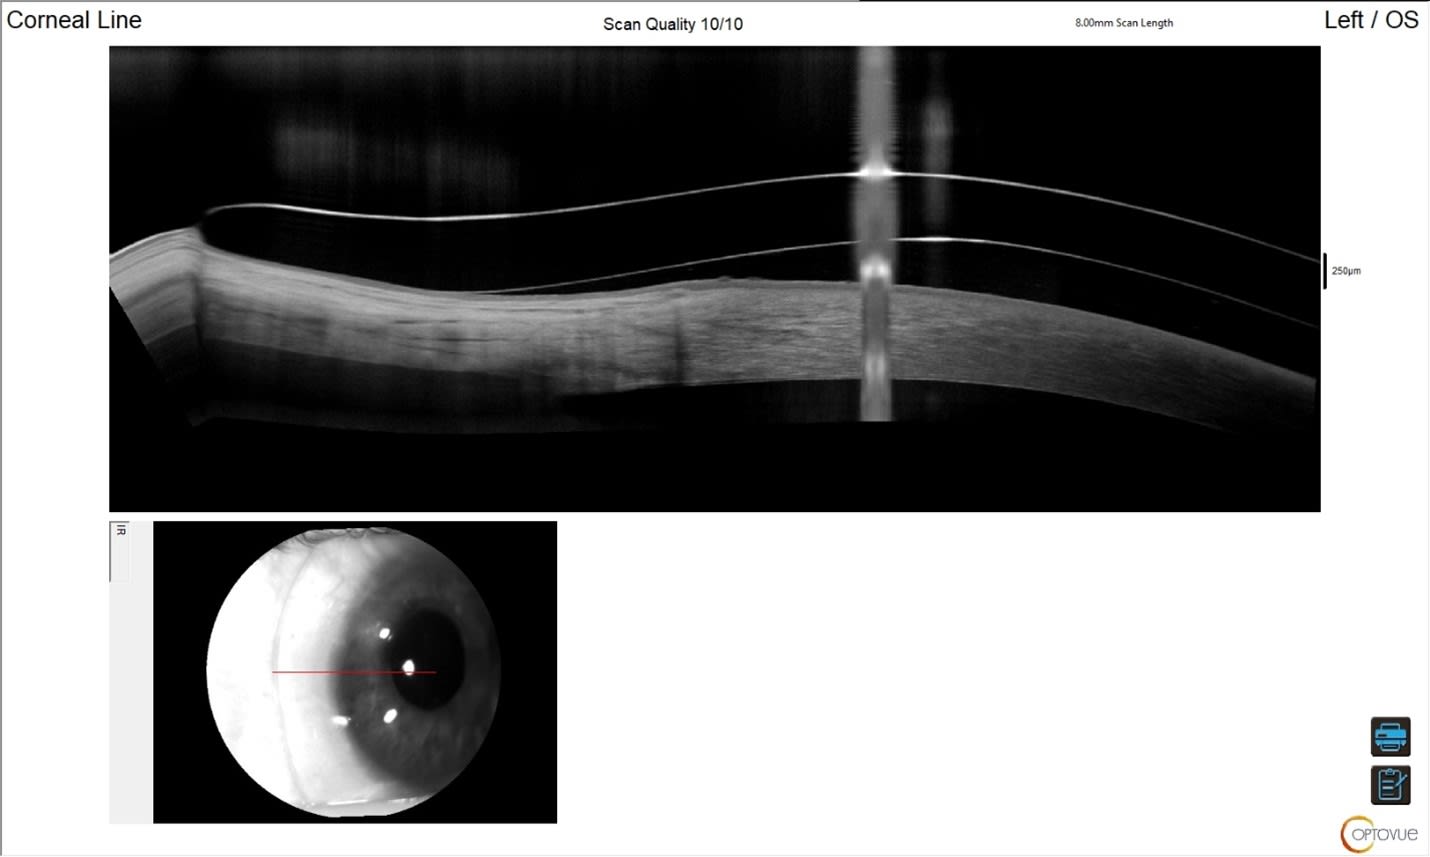

At dispense, AL’s vision was 20/20+2 OS. The anterior segment OCTs are shown below (Figures 2 through 6). We imaged scleral prosthetic lenses centrally and in four principal meridians at the haptics to ensure an optimal fit.